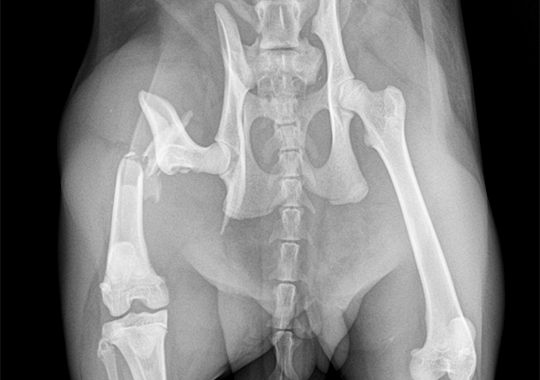

십자인대 파열 수술 전

십자인대 파열 수술 후

정형외과 케이스

본원은 실력 있는 전문 의료진과 최첨단 시설로 정형외과에서 좋은 예후들을 보여드리고 있습니다. 강아지에게서 쉽게 발생하는 슬개골 탈구, 십자인대 단열 뿐 아니라 다양한 고난도 케이스를 다루고 있으며, 특히 골절 수술은 회복률이 높고 타원 수술 후, 유합부전으로 본원에 내원하여 재수술에 성공한 사례가 많습니다.